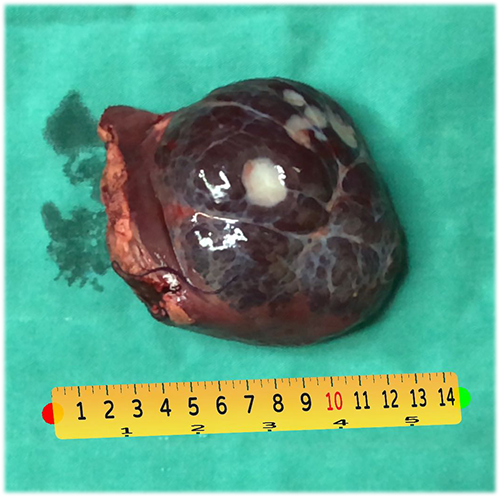

肝血管瘤--左肝外侧叶切除